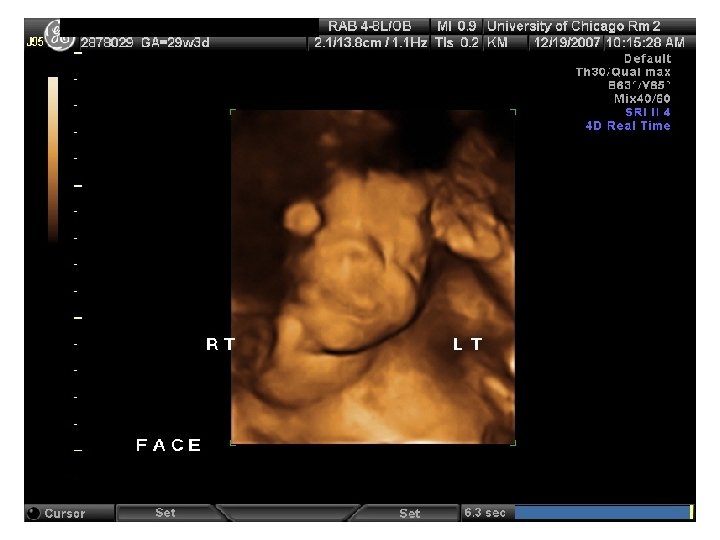

QUIZ What is Your Diagnosis? Case: Patient J. F. 30 years old, at 32 week gestation. Presented with the following pictures.

Answer: a) Trisomy 21 b) Non-immune Hydops c) Paravo virus Infection